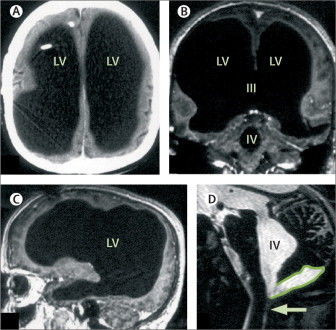

Có lẽ ai cũng sẽ nghĩ vị bác sĩ kia vui miệng trêu bệnh nhân cho đến khi nhìn thấy ảnh chụp cắt lớp này. Lớp dịch đã nuốt hết não, chỉ để lại phần vỏ não chứa các neuron thần kinh.